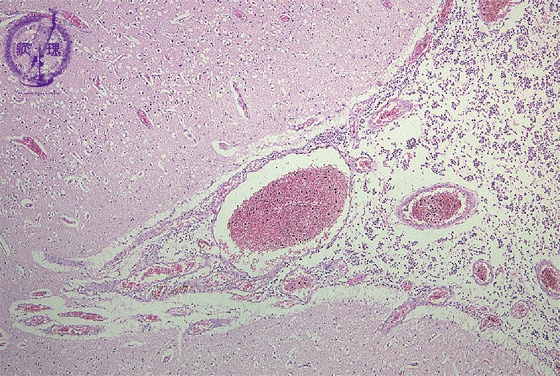

Microscopic findings (H.E. low magnification): Extensive infiltration of inflammatory cells detected in the subarachnoidal spaces but not in the cortex.